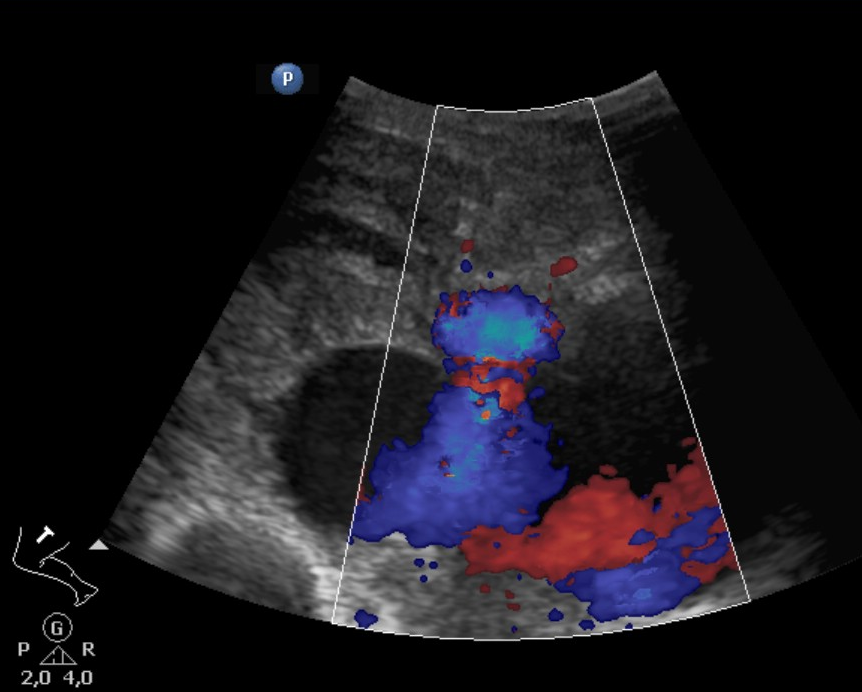

• Similar to the limbs, neck or chest after a heavy impact abdominal vascular injuries could also develop. They could be detected by US however CT provides a more reliable diagnosis.

• A knife falling from a kitchen table stuck into the right thigh of an 18 year old young man. Increased femoral circumference and pulsating mass were seen. In the upper image with femoral Duplex sonography pseudoaneurysm of the femoral artery is detected

In the middle with a CT angiography the pseudoaneurysm shows contrast enhancement.

In the lower image 3D reconstruction of the CTA

11. A knife falling from a kitchen table stuck into the right thigh of an 18 year old young man. Increased femoral circumference and pulsating mass are seen. In the upper image with femoral Duplex sonography pseudoaneurysm of the femoral artery is detected In the middle with a CT angiography the pseudoaneurysm shows contrast enhancement. In the lower image 3D reconstruction of the CTA